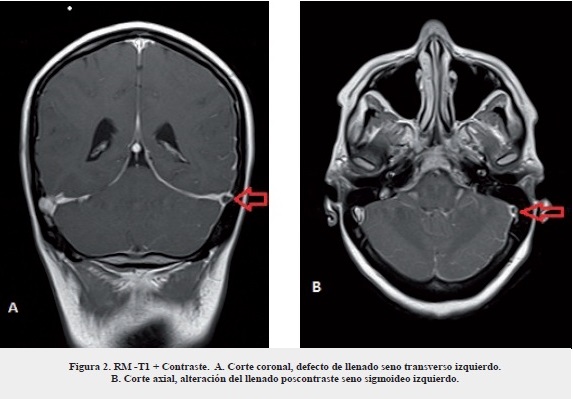

La paciente fue referida a la Fundación Centro Colombiano de Epilepsia y Enfermedades Neurológicas-FIRE por presentar cefalea occipital pulsátil de intensidad moderada de un mes de evolución asociado con náuseas, emesis, fotofobia, sonofobia, sin antecedentes de trauma craneoencefálico, ni enfermedades autoinmunes, sin historia de amenorrea, tampoco de abortos (G 0 P0 A0). A la evaluación física se observó en regular estado músculo nutricional, con signos vitales en metas FC: 82 latidos por minuto, FR: 18 respiraciones por minuto, normotensa con una presión arterial de 110/60 mm Hg, temperatura: 36,5 grados centígrados, peso 46 kg. El examen neurológico es normal sin presencia de signos patológicos. Como diagnóstico inicial se consideró el diagnóstico cefalea con signos de alarma. Se le ordenó una resonancia magnética cerebral (RM) 1,5 tesla que mostró una trombosis aguda del seno transverso y sigmoideo izquierdo (figura 1,2) punción lumbar con presión de apertura elevada. La prueba de embarazo fue negativa, hemograma con anemia leve, normocítica, normocrómicas, leucocitosis 16.490 mm3, sin trombocitos, nitrógeno ureico, creatinina, glucemia, tiempos de coagulación, proteinograma normales. Se inició anticoagulación con enoxaparina, previamente se realizaron paraclínicos de extensión para determinar causa de trombosis venosa cerebral, reportando proteína S por ELISA disminuida; factor V de Leiden, proteína C, antitrombina III y factor VIII normal, siklemia negativa, anticoagulante lúpico negativo, anticardiolipinas IgG e IgM negativa, anticuerpos antinucleares negativos; panangiografía cerebral comprueba trombosis del seno transverso y sigmoideo izquierdo (figura 3). Posterior al tratamiento, la paciente inició mejoría gradual a su estado, a los 14 días de estancia hospitalaria fue enviada a su casa con anticoagulación ambulatoria con enoxaparina subcutánea por 2 semanas y luego manejo con anticoagulación oral.

Para el diagnóstico de TSVC se debe partir de una minuciosa evaluación clínica y sospechar cuando se está ante la presencia de síntomas como cefalea, vómito o nauseas, signos de hipertensión endocraneana, papiledema, estados de hipercoagulabilidad, embarazo, puerperio o utilización de anticonceptivos hormonales19. En el caso de las ayudas diagnósticas, la utilización de la resonancia magnética nuclear permite ver con mayor facilidad la oclusión del seno venoso20.